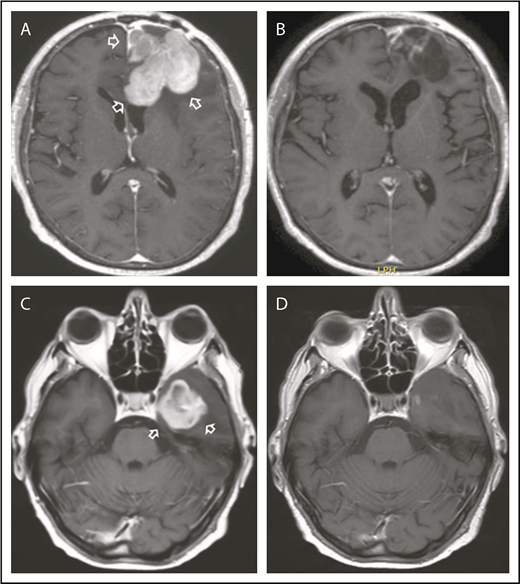

Per protocol, the first 10 enrolled patients received a course of R-CHOP without NGR/hTNF; after this course, 1 patient had PR, 7 had stable disease, and 2 experienced PD (details in supplemental Table 1). The best response to NGR-hTNF/R-CHOP combination was CR in 8 patients (examples in Figure 2) and PR in 1, with an ORR of 75% (95% confidence interval, 51-99); three patients experienced PD (Figure 3). Interestingly, one of the patients who experienced PD after the first course of R-CHOP (patient #8) achieved PR after NGR-hTNF/R-CHOP (after the second course of the experimental treatment), which was confirmed after the fourth and sixth courses. The predetermined activity threshold of the first-step analysis of at least 4 responses in the first 12 registered patients was largely achieved. The best response was achieved after the second course in 6 patients and after the fourth course in 3 patients. All the best responses were confirmed by a second MRI performed 6 weeks later. Consolidation in responding patients was WBRT in 2 patients, ASCT in 3, lenalidomide maintenance in 2, and combinations of these therapies in 2. Response lasted >6 months in all responders (median, 10 months; range, 7-14 months). Six responders experienced relapse at 7 to 12 months; 2 responders (patient #2 and patient #10 in Figure 3) died of complications related to progressive neurological impairment, without evidence of relapsing lymphoma. Four patients are alive at a median follow-up of 19 months (range, 14-28 months).

Examples of responses to R-CHOP preceded by NGR-hTNF. (A) Gadolinium-enhanced T1 weighted scan shows a large homogeneous enhancing lesion in the left frontal lobe (arrows) in a 62-year-old woman at the second relapse after high-dose methotrexate and after salvage high-dose ifosfamide-based therapy; disease was refractory to previous lines. (B) Tumor regression after 2 courses of experimental treatment. (C) Gadolinium-enhanced T1 weighted scan shows a large enhancing left temporal lesion (arrows) in a 65-year-old man at the second relapse after high-dose methotrexate and after salvage whole-brain irradiation. (D) Tumor regression after 2 courses of experimental treatment.